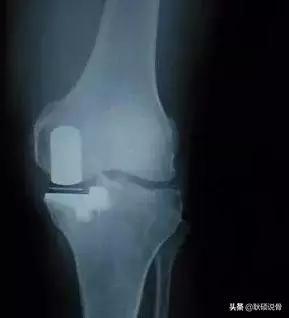

第三种,单髁置换术(UKA)。适用于关节内畸形,而周围软组织韧带等结构没有破坏。这种置换理念如今被越来越多的专家认可。因为只置换了1/3的关节面,可以保留交叉韧带、内测副韧带、外侧副韧带。术后回归自然状态。也就是说患者术后是靠自身韧带的引导进行膝关节活动。